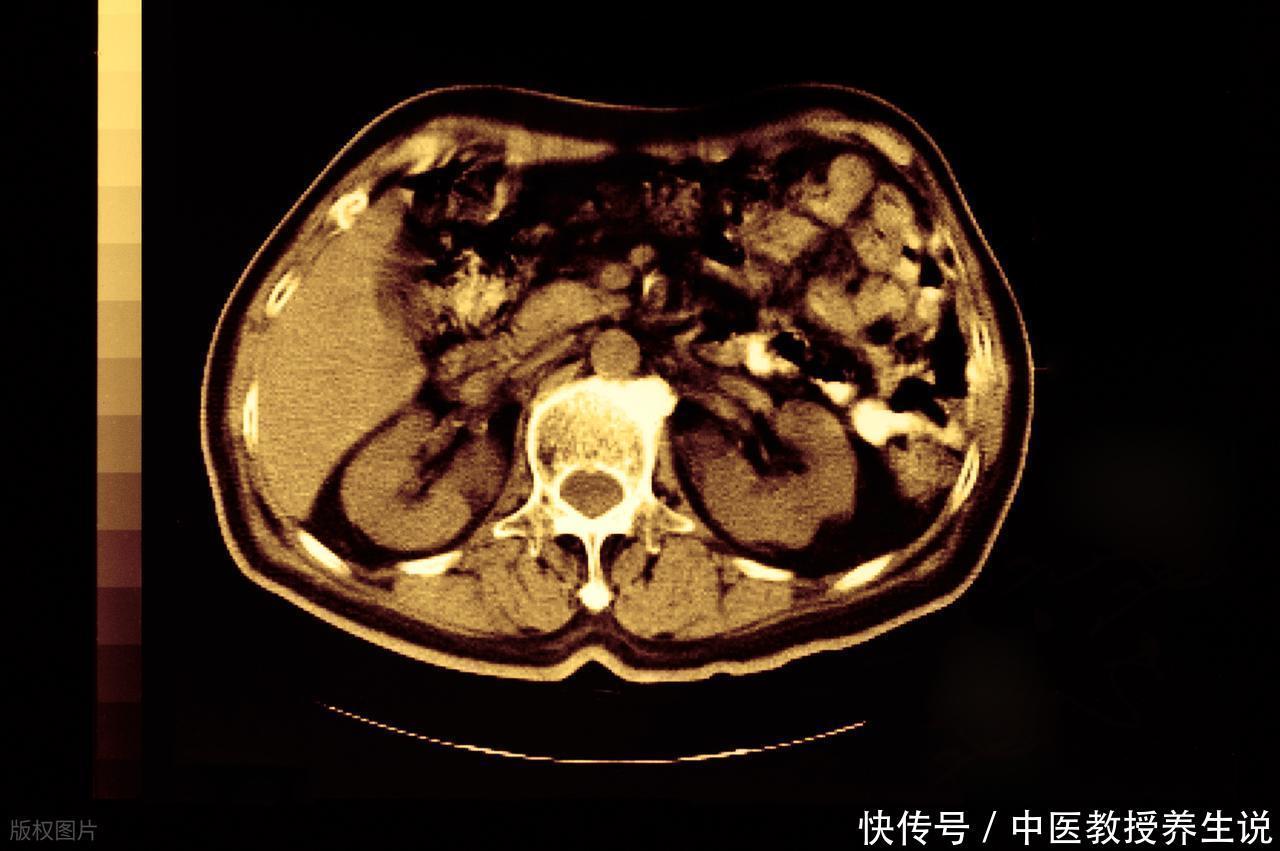

现代医学影像的筛查网越织越密,CT、B超的精度让以往无法察觉的微小异常也无处遁形。肝脏作为人体最大的“化工厂”,内部结构复杂,偶尔出现一些无碍功能的“小插曲”实属常见。许多在体检中被“揪出来”的小个肝腺瘤,并非身体拉响了严重警报,更像是高精度设备捕捉到的、原本就可能存在的“背景信息”。它们静静地待在那里,数年甚至数十年都没有动静,若非一次偶然的检查,或许终其一生都不会被发现。

多数情况下,直接冲向手术台切除并非最佳选项。贸然“动刀”本身就意味着麻醉风险、创伤应激与漫长的恢复期。对待直径小于5厘米且没有特殊表现的肝腺瘤,医学界的主流共识更倾向于“主动监测”。

良性为大概率: 绝大多数孤立的小肝腺瘤,其内在性质是温和的,恶变的可能性相当低。它更像皮肤上的痣,是组织的一种良性增生,而非一颗“定时炸弹”。

观察代替切除: 所谓观察,并非放任不管。它是一种积极的随访策略,通常建议每隔6到12个月进行一次影像学复查,动态追踪其大小、形态有无变化。只有在持续、明显增大时,才需要重新评估干预的必要性。